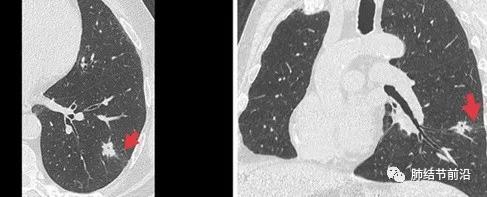

也有一些CT表现,可以间接预测STAS的可能。首先,STAS很少发生于磨玻璃结节,主要发生于实性或实性结节为主的肺结节。CT特征还有:结节有毛刺,有卫星灶,胸膜粘连,磨玻璃条带,以及不清晰的瘤-肺边界。

STAS显示为结节外侧的磨玻璃条带。